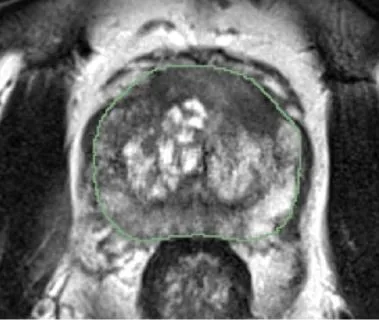

Bashkanov, O; Rak, M; Meyer, A; Engelage, L; Lumiani, A; Muschter, R; Hansen, C

Automatic detection of prostate cancer grades and chronic prostatitis in biparametric MRI Journal Article

In: Computer Methods and Programs in Biomedicine, vol. 239, pp. 107624, 2023, ISSN: 0169-2607.

abstract = {Background and objective:With emerging evidence to improve prostate cancer (PCa) screening, multiparametric magnetic prostate imaging is becoming an essential noninvasive component of the diagnostic routine. Computer-aided diagnostic (CAD) tools powered by deep learning can help radiologists interpret multiple volumetric images. In this work, our objective was to examine promising methods recently proposed in the multigrade prostate cancer detection task and to suggest practical considerations regarding model training in this context. Methods:We collected 1647 fine-grained biopsy-confirmed findings, including Gleason scores and prostatitis, to form a training dataset. In our experimental framework for lesion detection, all models utilized 3D nnU-Net architecture that accounts for anisotropy in the MRI data. First, we explore an optimal range of b-values for diffusion-weighted imaging (DWI) modality and its effect on the detection of clinically significant prostate cancer (csPCa) and prostatitis using deep learning, as the optimal range is not yet clearly defined in this domain. Next, we propose a simulated multimodal shift as a data augmentation technique to compensate for the multimodal shift present in the data. Third, we study the effect of incorporating the prostatitis class alongside cancer-related findings at three different granularities of the prostate cancer class (coarse, medium, and fine) and its impact on the detection rate of the target csPCa. Furthermore, ordinal and one-hot encoded (OHE) output formulations were tested. Results: An optimal model configuration with fine class granularity (prostatitis included) and OHE has scored the lesion-wise partial Free-Response Receiver Operating Characteristic (FROC) area under the curve (AUC) of 1.94 (CI 95%: 1.76–2.11) and patient-wise ROC AUC of 0.874 (CI 95%: 0.793–0.938) in the detection of csPCa. Inclusion of the auxiliary prostatitis class has demonstrated a stable relative improvement in specificity at a false positive rate (FPR) of 1.0 per patient, with an increase of 3%, 7%, and 4% for coarse, medium, and fine class granularities. Conclusions: This paper examines several configurations for model training in the biparametric MRI setup and proposes optimal value ranges. It also shows that the fine-grained class configuration, including prostatitis, is beneficial for detecting csPCa. The ability to detect prostatitis in all low-risk cancer lesions suggests the potential to improve the quality of the early diagnosis of prostate diseases. It also implies an improved interpretability of the results by the radiologist.},